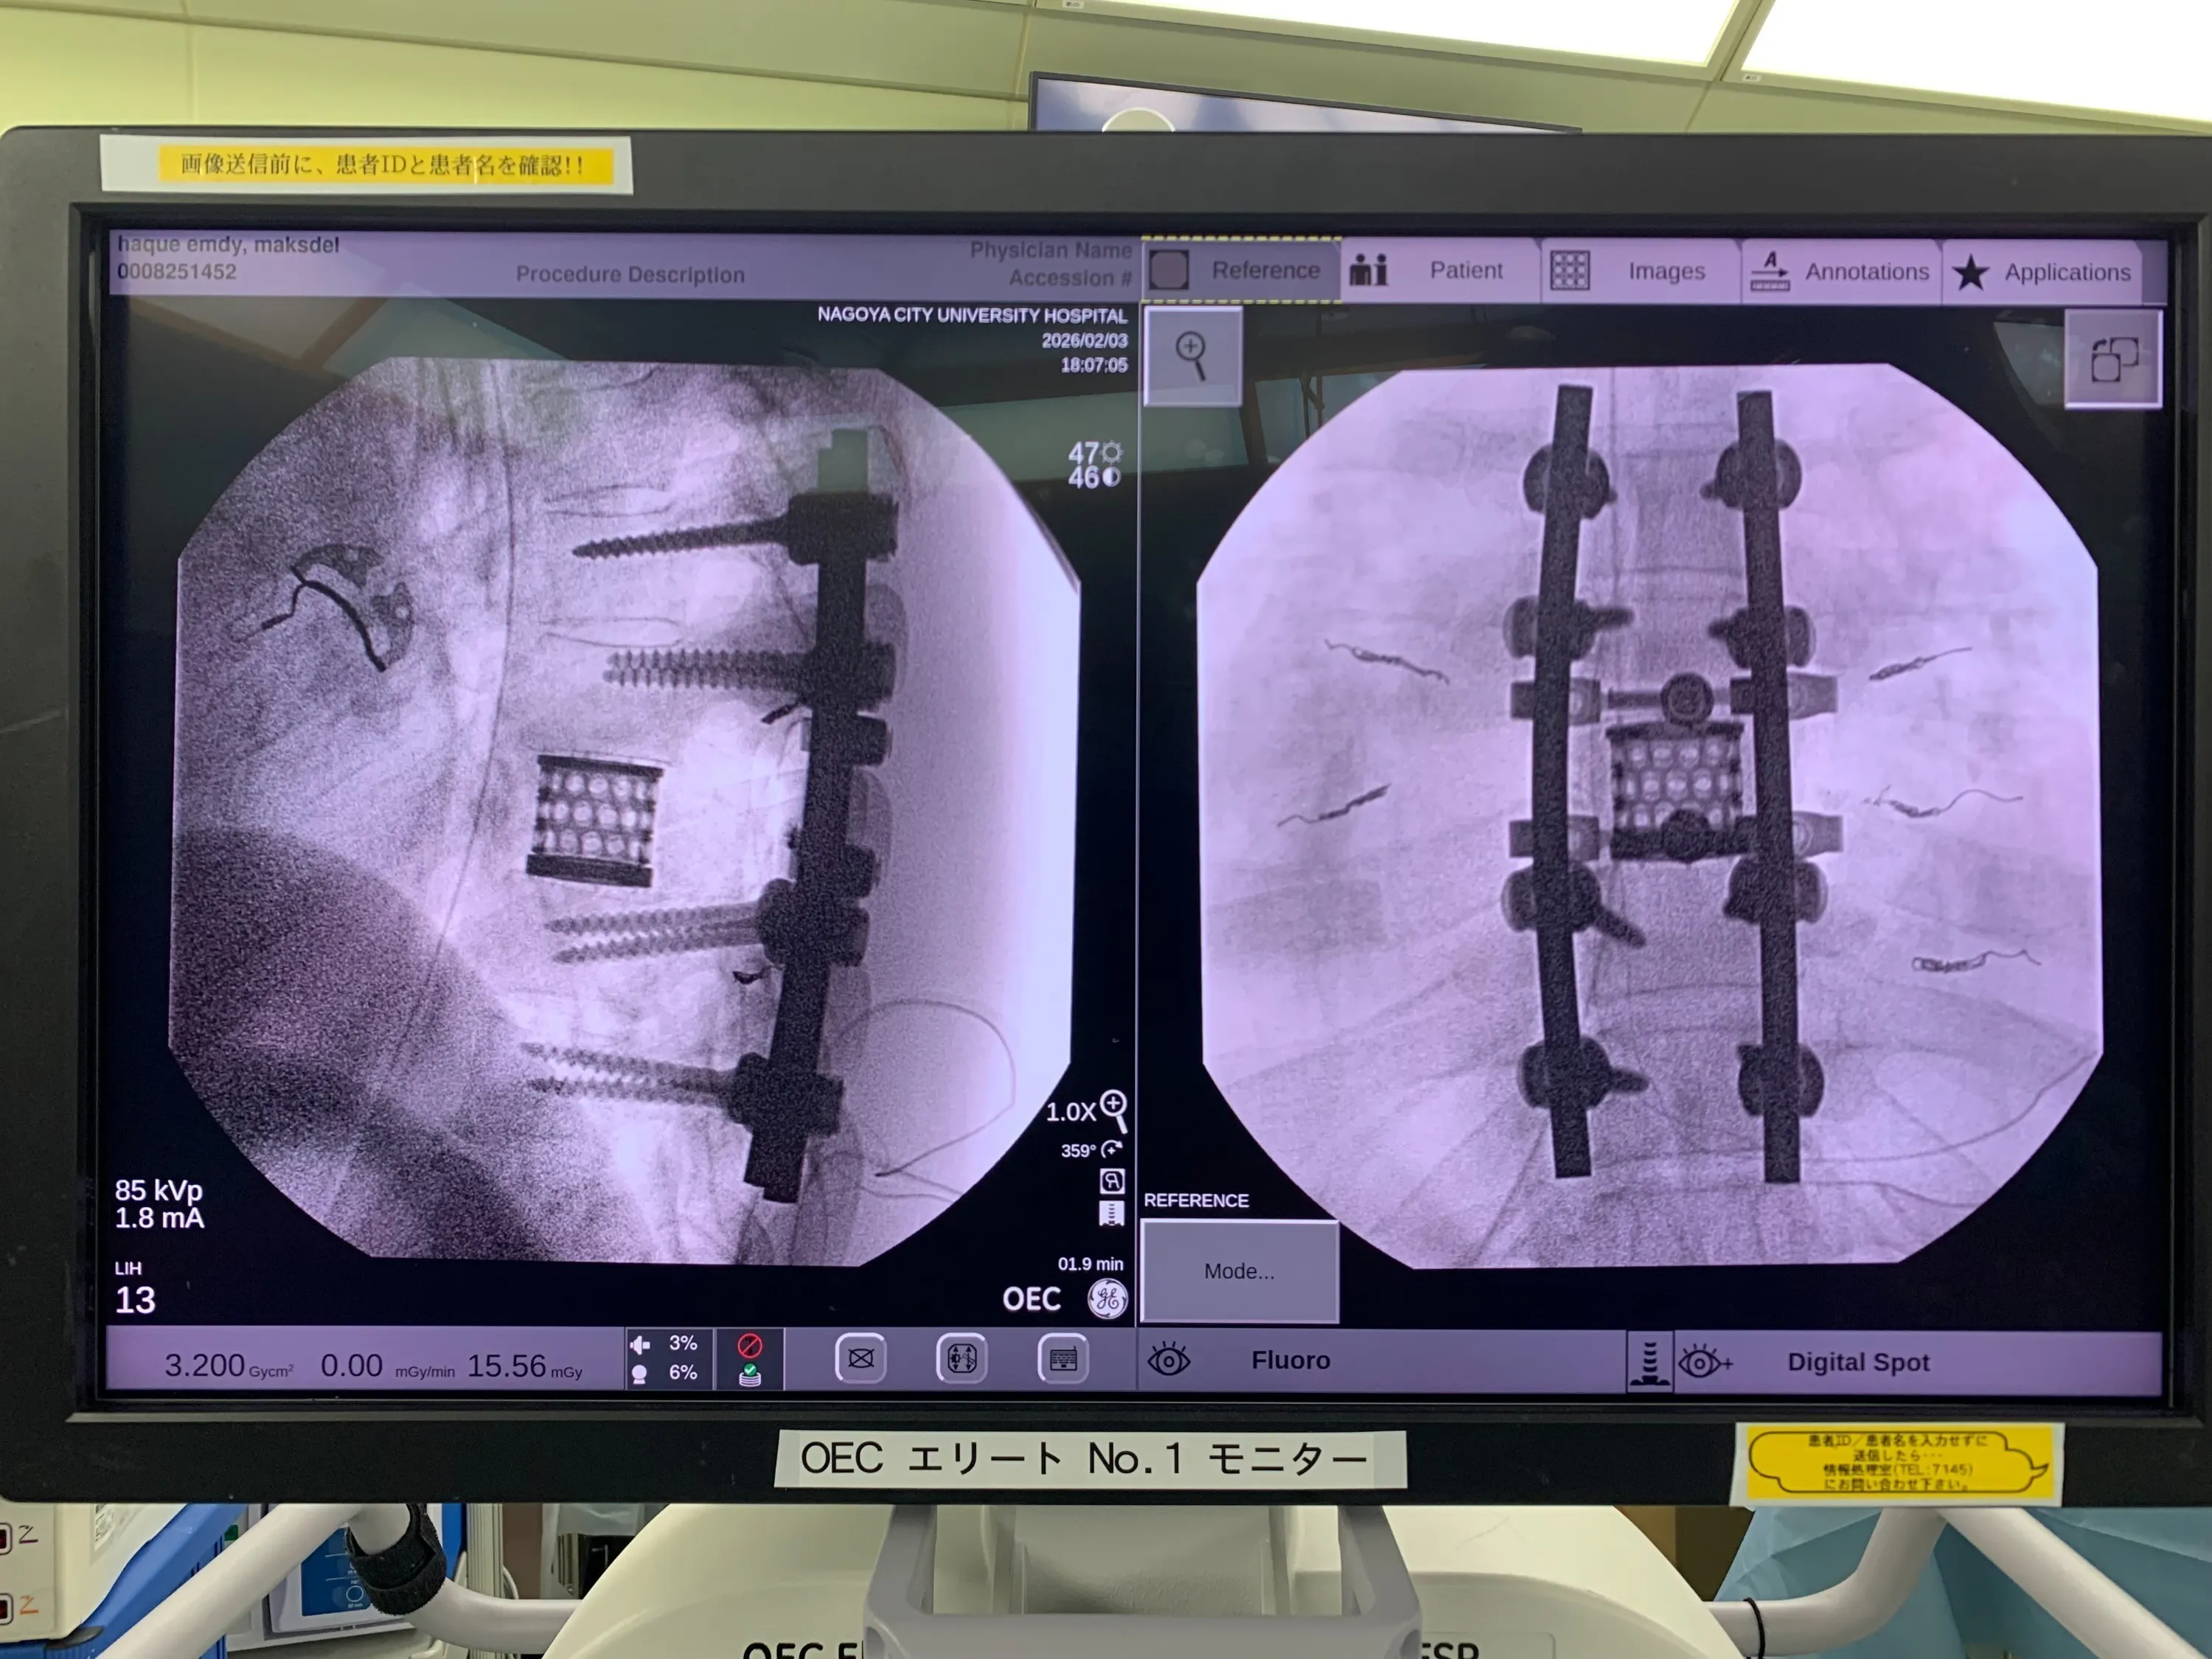

そして2025年2月3日。

ハクさんは 7時間を超える大きな手術 を受けました。

脊椎の腫瘍を取り除く手術はとても難しく、日本でも限られた医師しか行うことができない高度な手術です。

母国バングラデシュでは、この治療を受けることはできません。

2026年2月 脊椎腫瘍の手術を実施

定期健診に行きました

2026/04/16 20:57Last Friday, I had a routine checkup with Professor Murakami at Nagoya City University Hospital. He reviewed my X-ray and said that my condition is now good and will continue to improve day by day. However, the pain will persist, so I will need to take painkillers. Rehabilitation exercises should be done daily to speed up recovery.先週の金曜日に、名古屋市立大学病院で村上先生の定期診察を受けました。レントゲンを見ていただき、状態は良くなっていて、これからも少しずつ回復していくと言っていただきました。ただ、痛みはまだ続くので、しばらくは痛み止めを使いながら過ごす必要があります。また、回復を早めるために、リハビリは毎日続けるように言われました。 もっと見るハクです。近況をお伝えします